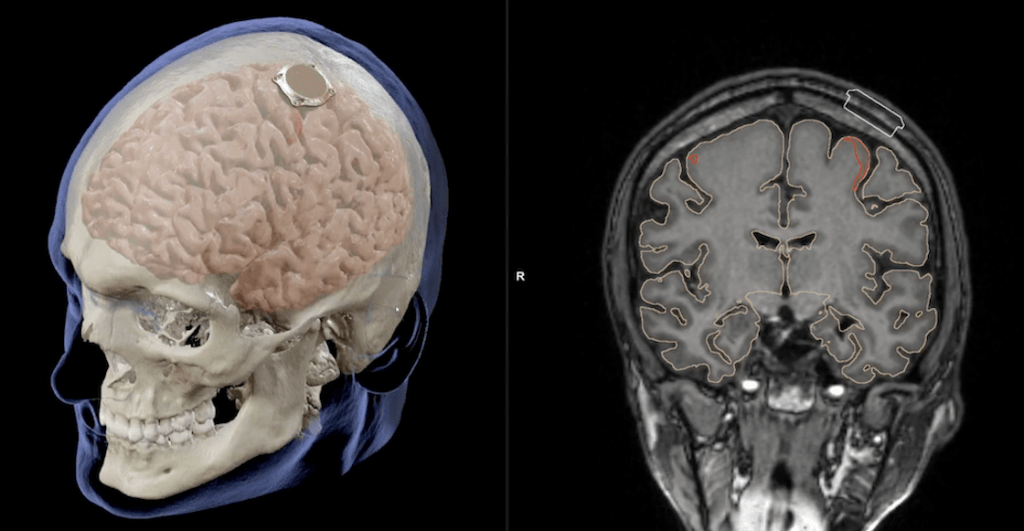

De acuerdo con la empresa de Elon Musk, los primeros voluntarios humanos del chip cerebral de Neuralink deberán ser personas que tengan cuadraplejía; que hayan perdido sus funciones motrices a causa de una lesión en la médula espinal o como una forma avanzada de Esclerosis

La razón por la que los primeros voluntarios humanos del chip cerebral de Neuralink tienen que tener una discapacidad motriz es que la empresa espera que su dispositivo pueda darles la posibilidad de controlar un cursor o un teclado “solo con sus pensamientos”.

En la primera van a probar los resultados del chip N1, su prometida interfaz controlada por impulsos cerebrales. Esperan que sea completamente invisible y que los 1,024 electrodos, conectados en 64 hileras funcionen a la perfección.

En la segunda van a estudiar al robot R1, que es el dispositivo que implanta el chip. En la tercera revisarán las funciones de la N1 User App, un software que transforma las señales cerebrales o los impulsos eléctricos en órdenes computacionales como escribir un mensaje o apuntar un cursor. Durante este estudio se probarán sus funciones y por supuesto, su seguridad.